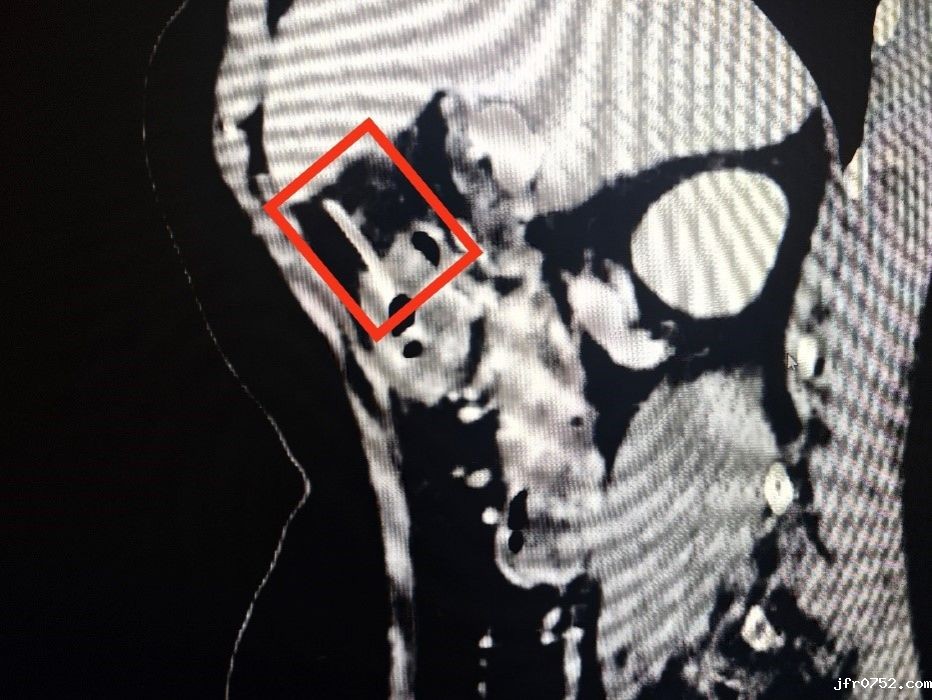

(CT显示长约5cm的鱼刺已经穿透胃壁)

原来,三日前,张大娘和家人边吃鱼边聊天时,没注意鱼刺就吞了下去,本人还没有感觉到异常,所以腹痛难忍时也没有跟医生说明。在为张大娘做了CT检查后,发现胃周腹腔内存在少量游离气体,CT室主任潘历波在查找导致气体产生的原因时,发现了已经穿透胃壁的异物。潘主任就此询问患者病史,有没有吞食过什么尖锐的东西,患者才想起腹痛前三天曾食用过鱼肉。

此时,刺透胃壁的鱼刺可能随时扎入肝脏,引起大出血,危及生命。面对这一棘手问题,黄山平主任考虑取出异物刻不容缓,立即给患者进行胃镜检查。在胃镜探查过程中发现,鱼刺一端已深深扎入胃窦前壁,鱼刺大部分均在胃壁里,仅有很小部分在胃腔内,造成“抓捕”困难,一不小心鱼刺可能会“溜出”胃壁。为此,黄山平主任团队凭借多年积累的丰富经验,精准使用内镜异物钳将鱼刺牢牢抓住,并将其完整拔出,过程顺利,患者腹痛立刻得到缓解。